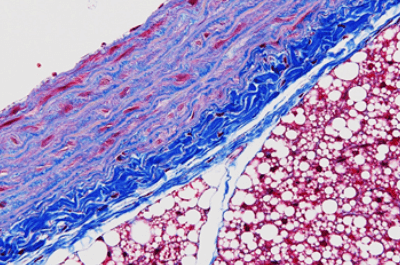

- 【結合組織の染色】

- 線維化病変、基底膜の観察など幅広い用途に用いられます。

| マッソントリクローム (MT)染色 | 膠原繊維が青く染まる